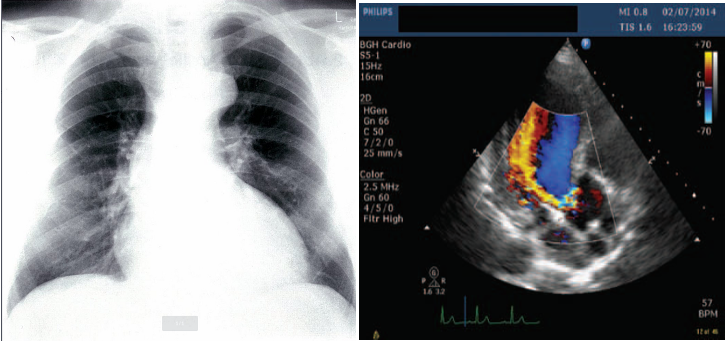

Investigations

- Echocardiography and Doppler (TTE): First-line diagnostic tool: assess the severity: LV dilatation.

- CXR:

- Cardiomegaly: Dilating ascending aorta.

- Pulmonary edema (Acute AR) with normal cardiac size.; crepitation

Imaging

A. Echocardiogram:

- Allows visualization of the origin of the regurgitant jet and its width, detection of aortic valve pathology and ventricular hypertrophy.

B. CXR:

- May demonstrate cardiomegaly.

- Dilated ascending aorta.

- Calcification may be seen.